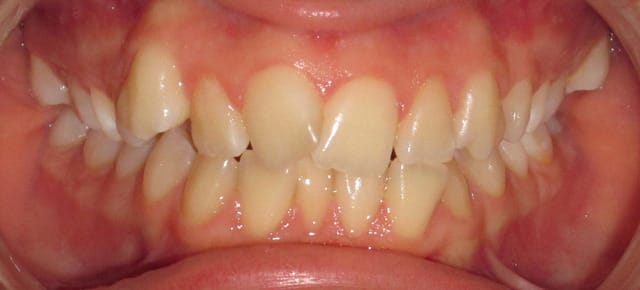

Avant opqvab - Eugenol

Bonjour à tous, patiente qui refuse catégoriquement l'implanto.

J'en ai bavé mais le résultat final est vraiment sympa.

Enfin la patiente et moi sommes très content.